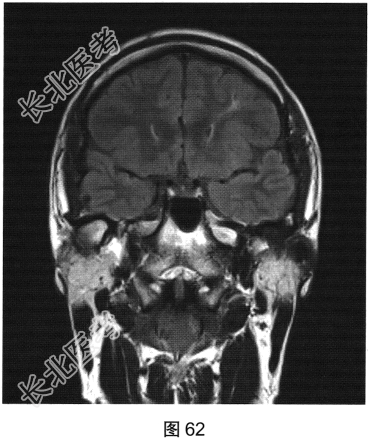

- 多项选择题2.[提示]患者行颅脑MRI检查,见图62、图63。根据患者病史及影像学检查, 提示其可能的诊断是( )

A、内侧颞叶癫痫左侧海马硬化

C、内侧颞叶癫痫右侧海马硬化

F、内侧颞叶癫痫双侧海马硬化